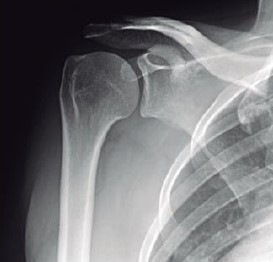

O exame de ombro, denominado de AP verdadeiro, é obtido com angulação do raio a 45° de medial para lateral, com o braço ao longo do corpo. Outra opção alternativa seria rodar o paciente até que a escápula fique encostada no filme e o raio incida perpendicularmente à escápula. Essa incidência tem como objetivo principal evidenciar a articulação glenoumeral e o espaço subacromial.

Enunciado 4113213-1

BONTRAGER,K. L; LAMPIGNANO, J. P. Manual prático de técnicas e posicionamento radiográfico. Rio de janeiro:Elsevier, 8 ed., 2014 (adaptado).

De acordo com a imagem é correto verificar que o posicionamento do paciente foi